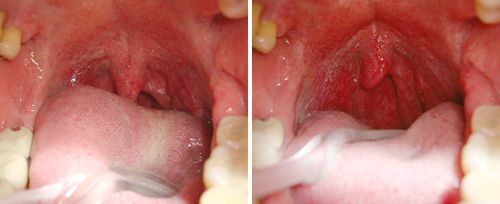

Fotona’s NightLase® therapy is a non-invasive, patient-friendly laser treatment for increasing the quality of a patient’s sleep. NightLase reduces the effects of sleep apnea and decreases the amplitude of snoring by means of a gentle, laser-induced tightening effect caused by the contraction of collagen in the oral mucosa tissue.